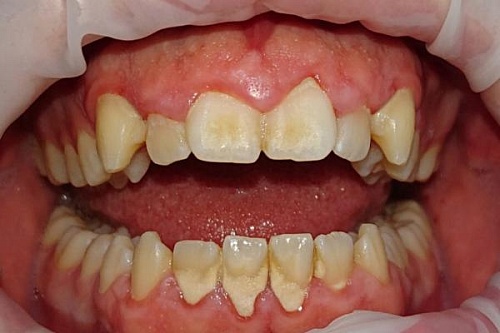

Профессиональная гигиена ультразвуком и Air Flow

Лечение зубов с использованием профессиональной гигиены, ультразвука и технологии Air Flow, мужчина 32 лет.

Профессиональная гигиена ультразвуком и Air Flow До

Профессиональная гигиена ультразвуком и Air Flow После